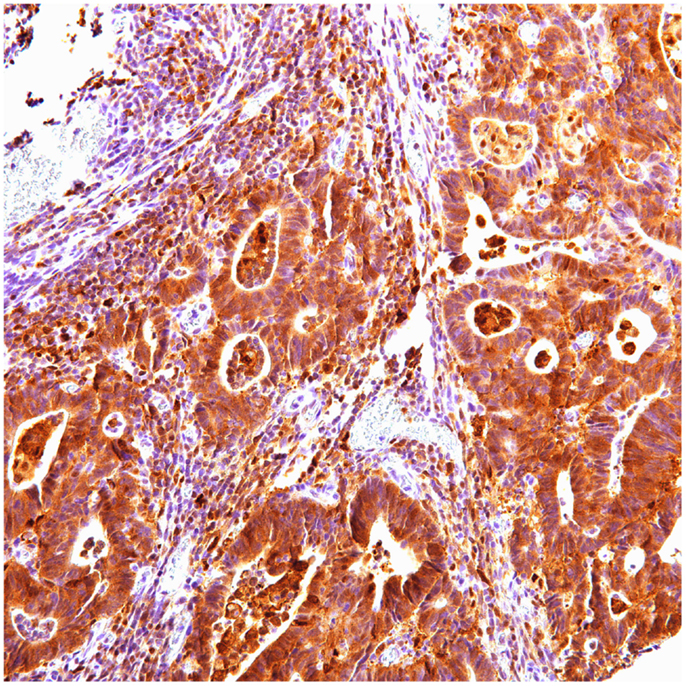

Figure 3. Ubiquitin cytoplasmic positive in colon carcinoma.

FIGURE 4

www.frontiersin.org

Figure 4. P62 cytoplasmic positive in colon carcinoma.

In colon carcinoma (45), positive p62 expression was noted [nucleus:13 (29%) and cytoplasmic 32 (71%)]. P62 nuclear and cytoplasmic stain was mostly of moderate to high intensity (2–3). Positive ubiquitin was present [nucleus: 26 (58%) and cytoplasmic 20 (44%)], with nuclear stain mostly of moderate to high intensity (2–3), and cytoplasmic stain mostly of low intensity (1).